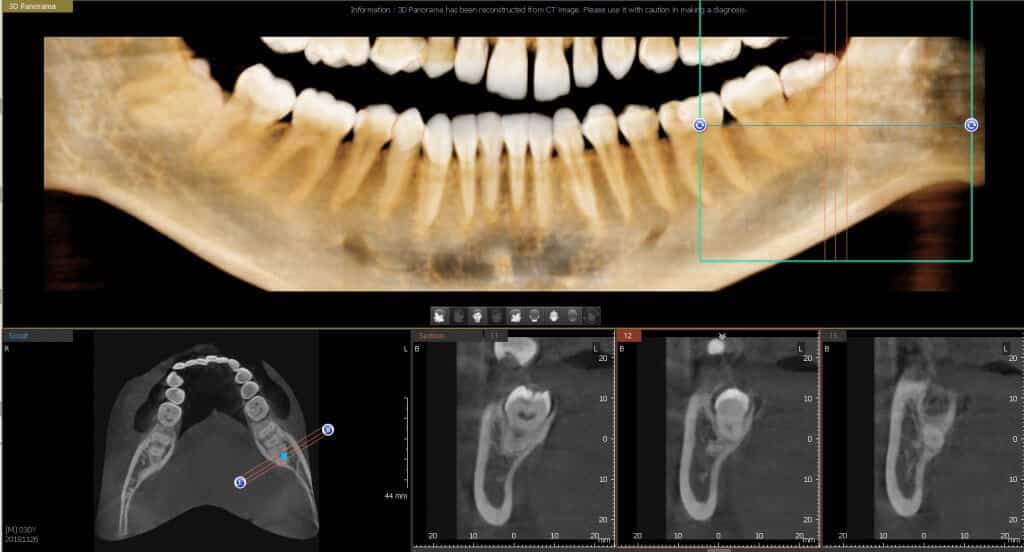

A fogászati CT, más néven CBCT (Cone Beam Computed Tomography), háromdimenziós képeket készít a fogakról, az állkapocsról és az állcsontokról. Ez a technológia nélkülözhetetlen az implantátumok behelyezésénél, az idegekhez közel elhelyezkedő bölcsességfogak eltávolításánál és a csontpótlásoknál. A fogászati CT Budapest MYdent rendelőjében minimalizálja a sugárterhelést, így a páciensek biztonságban érezhetik magukat.

A hagyományos panoráma röntgennel szemben a fogászati CT pontosabb és részletesebb képeket nyújt, ami lehetővé teszi a fogorvosok számára a pontos diagnózist és a megfelelő kezelési terv kidolgozását. A MYdent rendelőben használt PaX-i 3D technológia biztosítja, hogy a sugárzás mértéke minimális legyen, hasonlóan ahhoz, mintha a páciens egy rövid repülőúton venne részt.

Az eljárás menete egyszerű: a páciens a rendelőbe érkezik, ahol a szakértők előkészítik a CT felvételhez szükséges eszközöket. Az eljárás csupán néhány percet vesz igénybe, és azonnal rendelkezésre állnak a részletes képek, amelyek alapján a fogorvosok megtervezhetik a további lépéseket. A fogászati CT Budapest MYdent rendelőjében nem csak a diagnózis pontosságát növeli, hanem a kezelések sikerességét is jelentősen javítja.